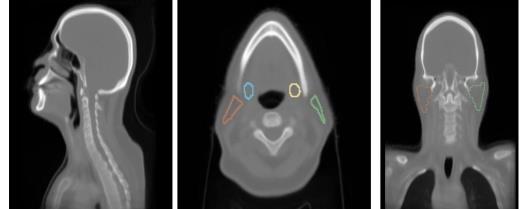

The anatomy normalization module addresses the challenge of anatomical variation across patients. By aligning key anatomical structures before feature extraction, we enable the model to learn features that are robust to patient-specific anatomical differences. This normalization is performed using deformable registration guided by anatomical landmarks and segmentation masks.

Our framework demonstrates superior performance in xerostomia prediction while providing clinically meaningful interpretations. The anatomy normalization significantly improves model generalization across diverse patient populations. The high-resolution CAMs successfully identify known risk factors such as parotid gland dose distributions and reveal novel spatial patterns associated with xerostomia risk.